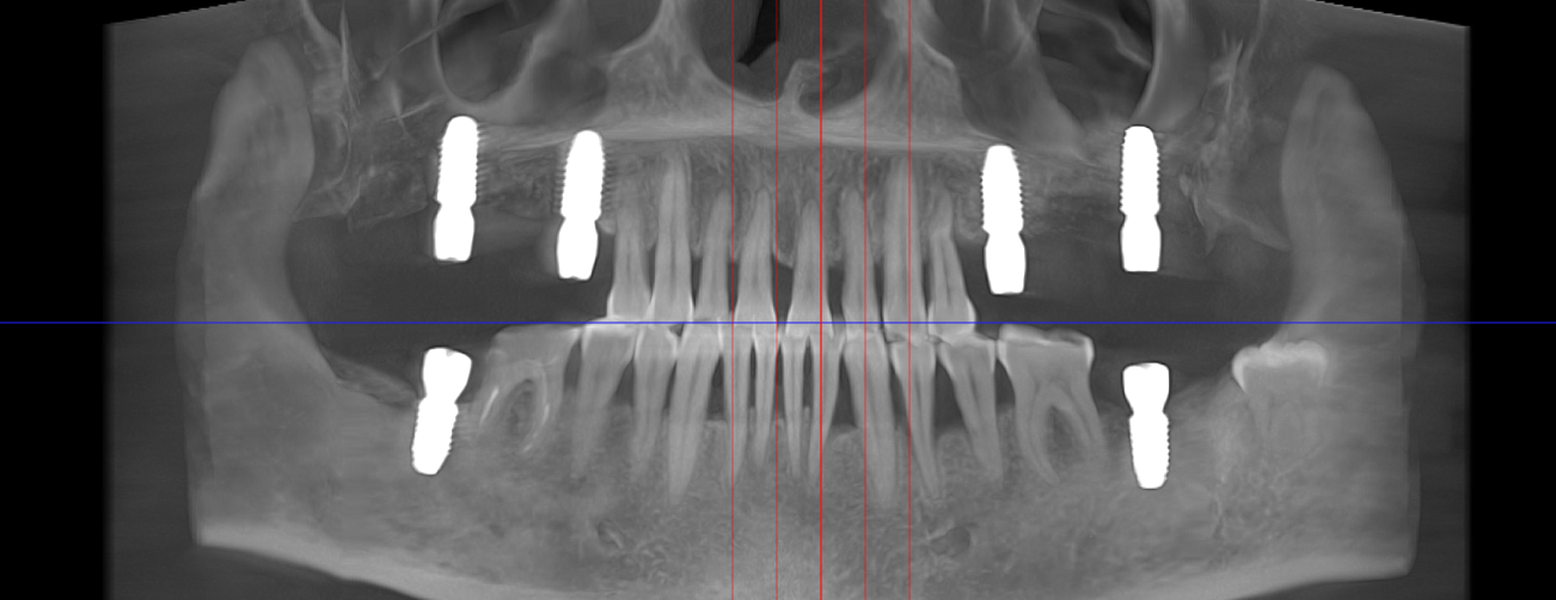

- Punte pe implanturi dentare – fixată pe 2 sau mai multe implanturi

- Șlefuirea dinților de susținere sau inserarea implanturilor

- Ai deja implanturi inserate și ai nevoie de restaurare protetică

- Tehnologie CAD/CAM și scanare digitală 3D